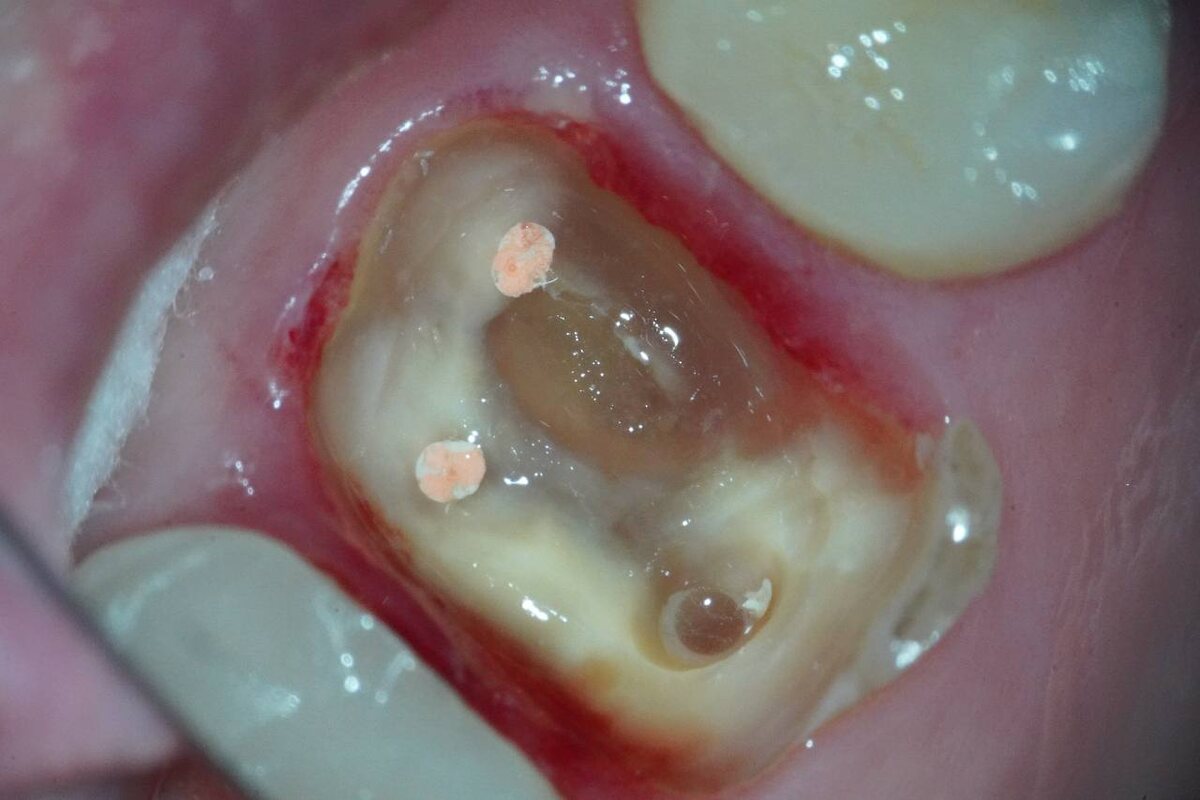

Клинический случай: пациентка обратилась с жалобами на изменение цвета 2.6 зуба.

По словам пациентки, более 10 лет назад на этом зубе была установлена керамическая вкладка E.max.

🔍 В ходе осмотра выявлены следующие изменения:

- Нарушение прилегания вкладки по границе «зуб–вкладка»;

- После удаления вкладки обнаружены деструктивные изменения тканей зуба — некротизированные массы, напоминающие резиноподобную консистенцию;

- Особенно выраженные изменения между мезиобуккальным 1 и мезиобуккальным 2 каналами (имеются визуальные различия по цвету);

- Разрушение твердых тканей ниже уровня краевой кости — сохранить зуб невозможно.